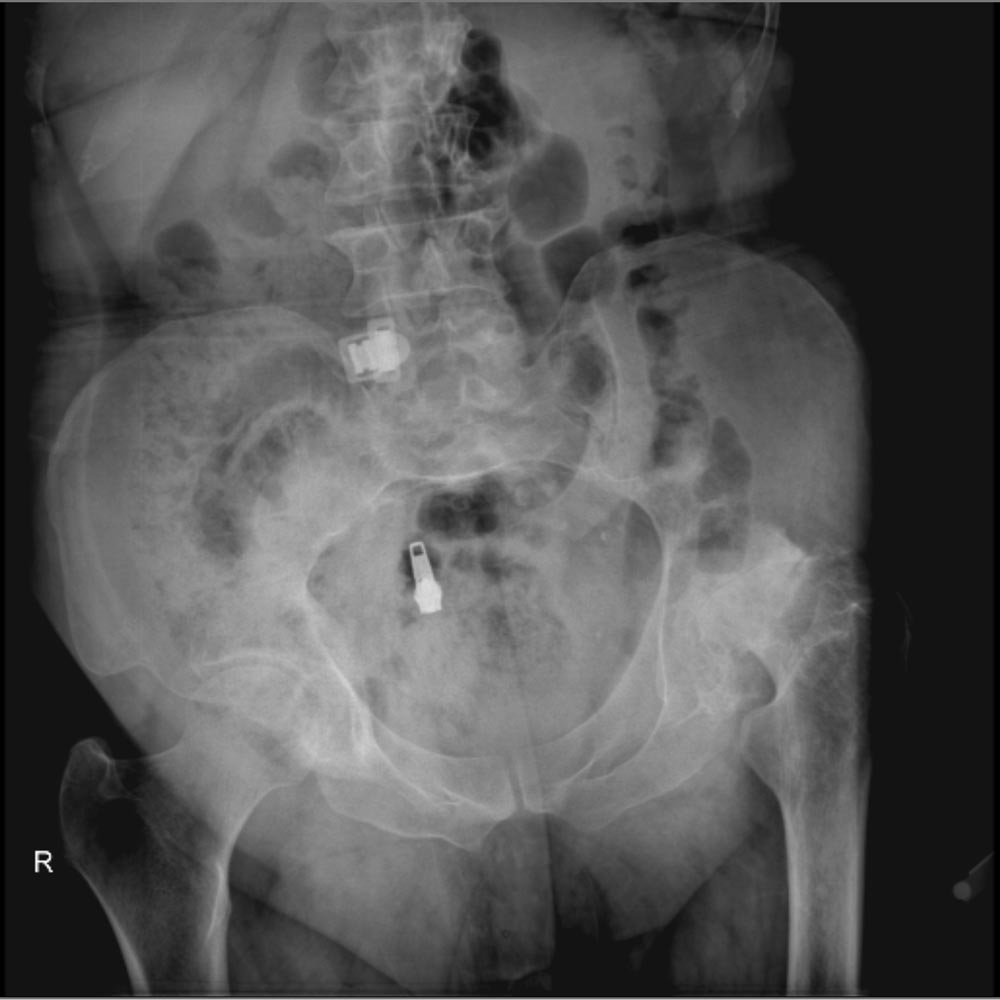

در نهایت، روش های تصویر برداری مثل رادیوگرافی به تشخیص بیماری کمک میکند. مهمترین روش تصویربرداری برای تشخیص ساییدگی لگن رادیوگرافی ساده است. تشخیص این بیماری نیاز به سی تی اسکن یا ام ار آی ندارد.

در تصویر رادیوگرافی از مفصل، چون غضروف نازک شده است فاصله مفصلی یا فاصله بین دو استخوانی که مفصل را تشکیل داده اند و در حد چند میلیمتر است کاهش پیدا میکند و در کناره های استخوان های تشکیل دهنده مفصل استخوان اضافی دیده میشود.

همچنین ممکن است کیست های استخوانی در بالای استابولوم یا در سر استخوان ران دیده شود.

در زیر تصاویری از عکس ساییدگی لگن در چند بیمار را میبینید. با کلیک بر روی هر کدام تصویر بزرگتری از آن را خواهید دید.